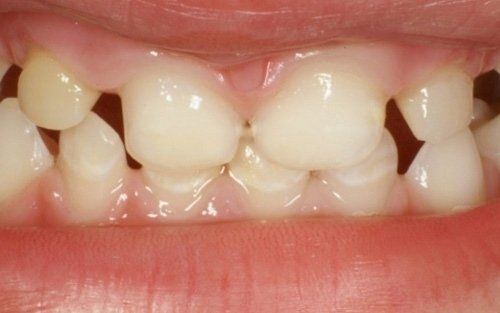

La carie nel bambino è una delle principali cause, insieme all’ortodonzia, di richiesta di intervento del dentista. La patologia ha una evoluzione particolarmente rapida in virtù della scarsità di smalto a difesa del dente da latte. Ciò comporta che, dal momento in cui il dente si ammala a quello in cui ne viene coinvolta la polpa (ovvero il nervo), il tempo sia veramente poco (vedi anche endodonzia pediatrica).